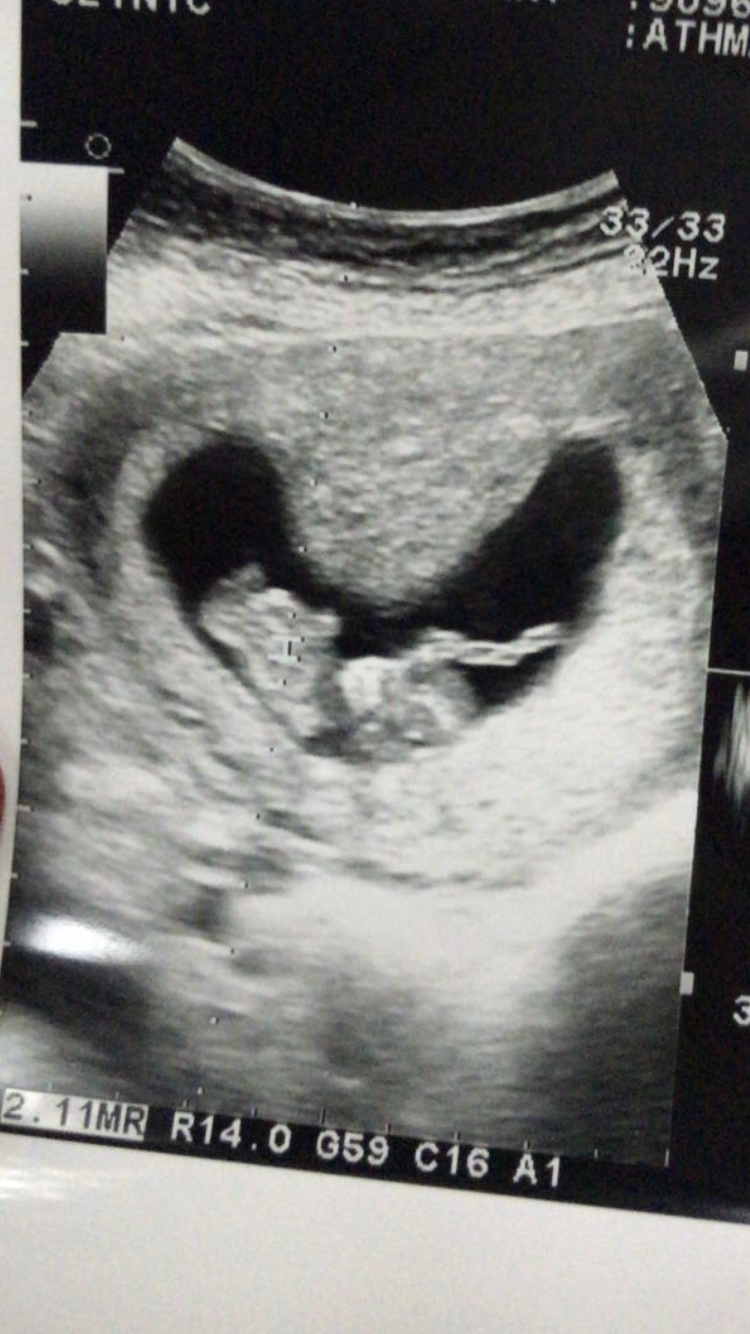

امس كان موعدي عندا الدكتوره قالت دخلتي الشهر الرابع وصرفت لي كالسيوم وحديد وفيتامينات بس قالت اذا باقي عندك استفراغ وغثيان لاتاكلينها الا بنص الرابع تقول عشانها قويه تعتبر ع المعده وانا معدتي تعبانه الله يعين وافتك من ذا الوحم

سالتها اذا راح يبين جنس الجنين اسوي اشاعه قالت ماانصحك الحين اصبري اسبوعين وتعالي ويارب يبان بعد اسبوعين

مرحبا والله اتابعكم من زمان ،، لكن مع الدوام والصغار والمدارس وماراجعت الا امس وكانت اول مراجعه لي وانا بالاسبوع ال ١١

التعب الي فيني طلع نقص فيتامين دال ،، وسويت سونار نبي خبراتكم ما قالت لي شنو فيني قالت تو الناس